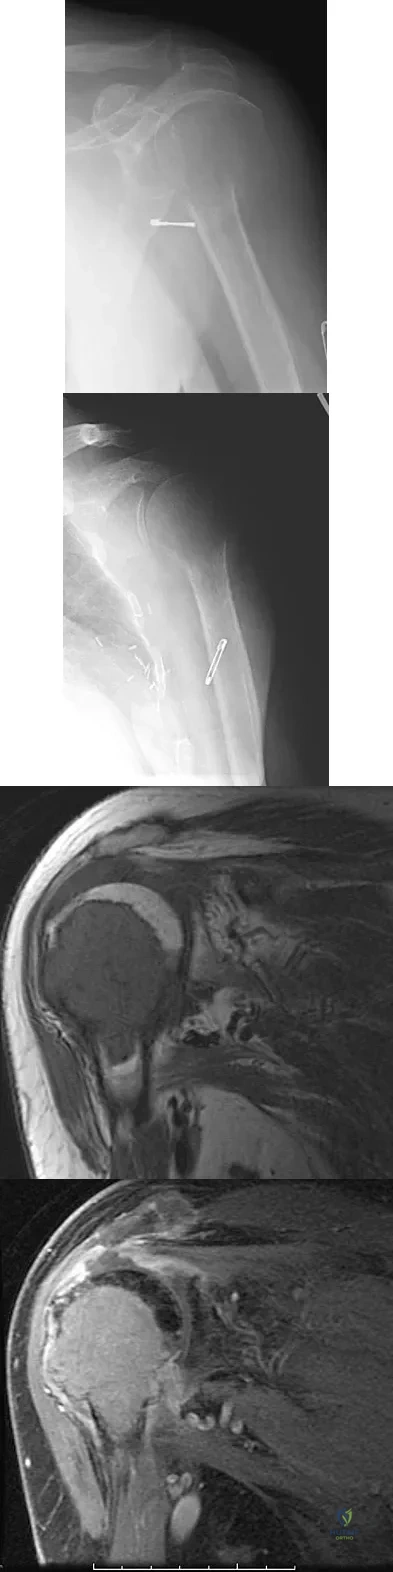

The humeral nonunion shown in Figure 27 is most likely to unite when using what method of treatment?

The radiograph shows an atrophic nonunion of the humeral shaft. The management of humeral nonunions has been studied with compression plates and bone graft, as well as intramedullary nailing and bone graft. Compression plating with bone graft results in the highest rate of union. Compression plating by itself is not adequate, given the bone loss and lack of callous in this nonunion. Pulsed electromagnetic fields is a viable option for hypertrophic nonunions where there is inherent stability. Intramedullary nailing does not provide as much compression and stability as that achieved with compression plating. Pugh DM, McKee MD: Advances in the management of humeral nonunion. J Am Acad Orthop Surg 2003;11:48-59.